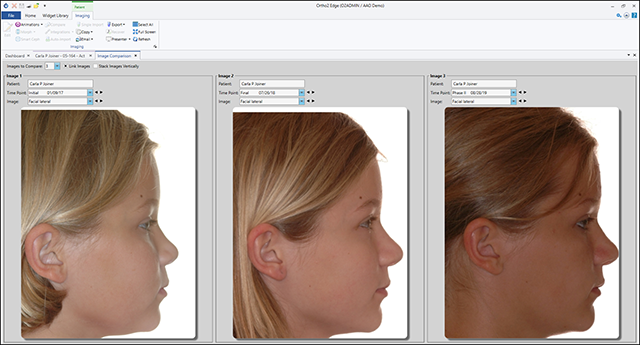

Fix photos with clear editing, and unlimited undos allows you to revert to the original image. Setup comparisons to view images from separate timepoints and show your patients the difference treatment has made. From importing images to timepoint comparisons, organizing and compiling photos, Edge Imaging does it all.

Make Presenting to Your Patients Easy

With many layout options, that include various timepoints, you can show your patients their progress throughout treatment. Customize the look of Edge Imaging to fit the needs of your office.

Timepoint and Image Morphing

Premier Imaging's morphing capabilities allow you to show patients stunning before, during, and after photos and presentations. Use these presentations to show prospective patients what can happen when they choose orthodontics.